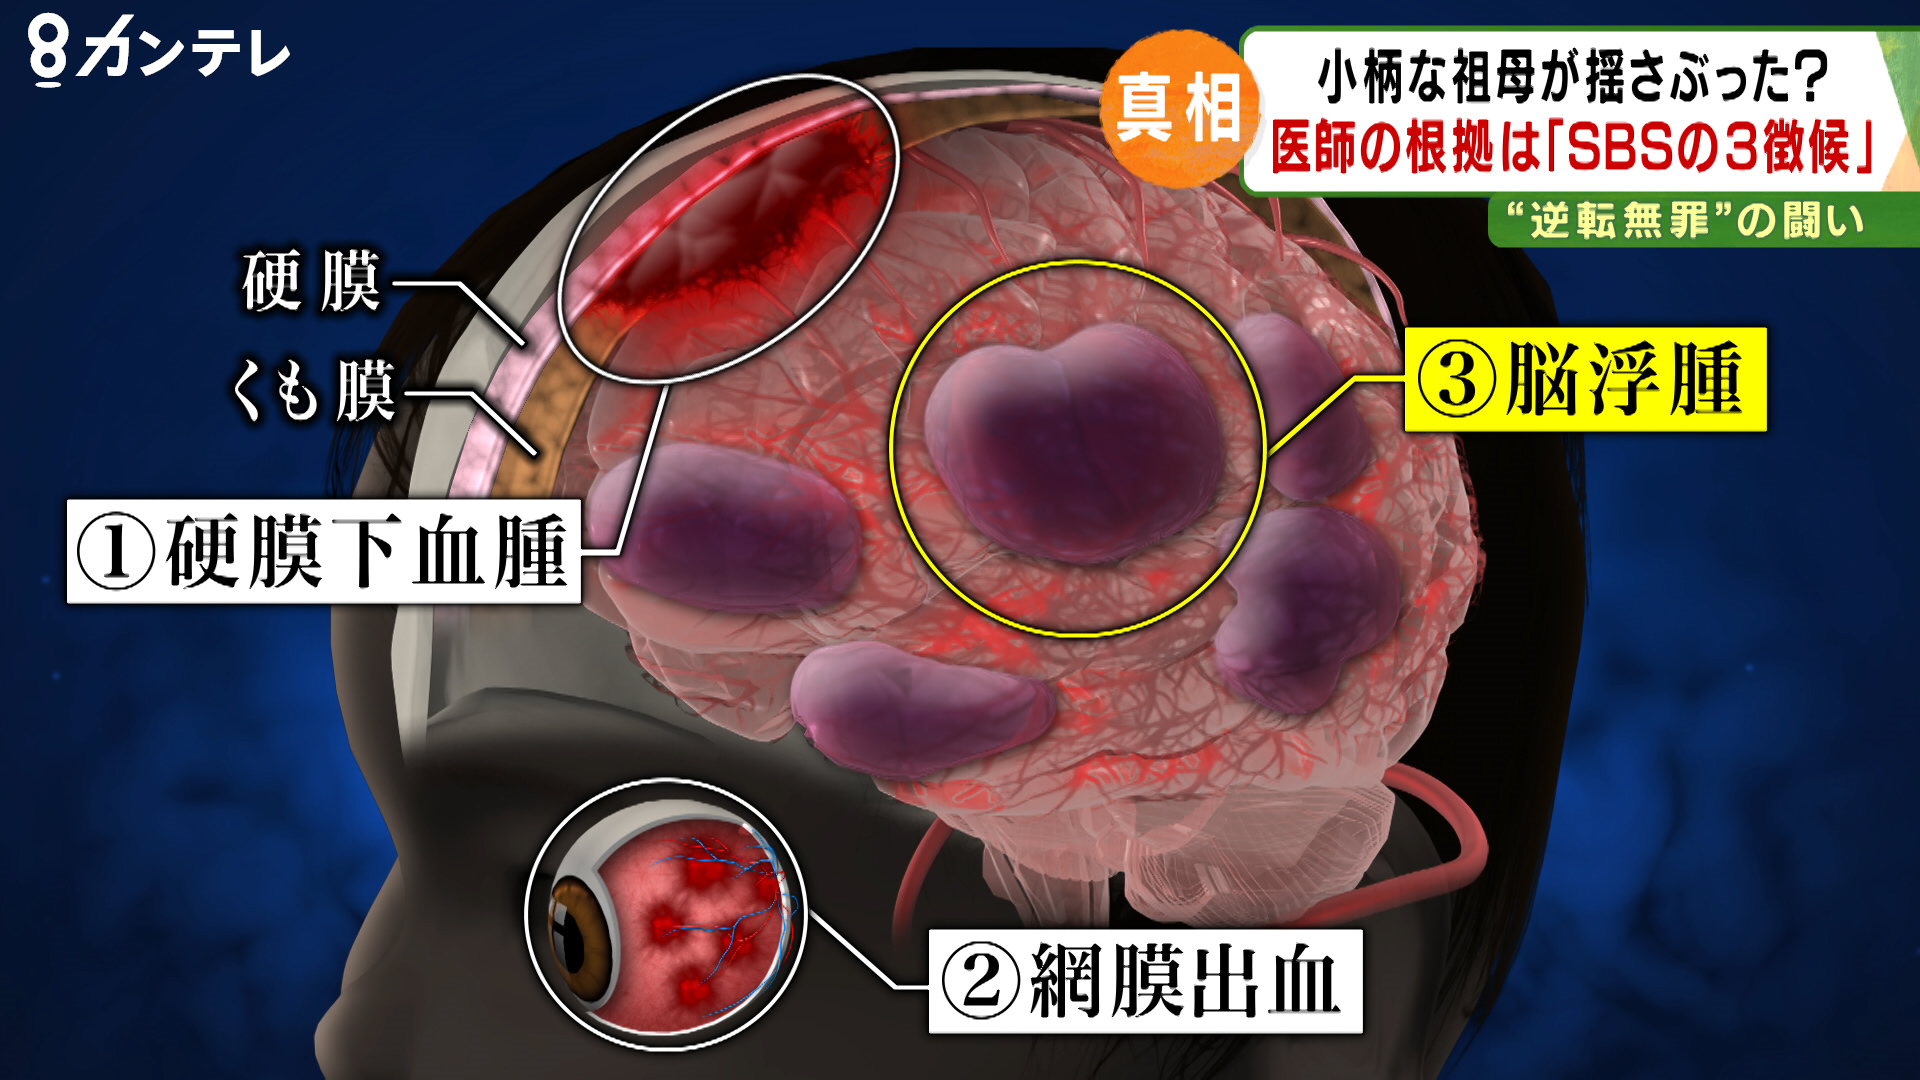

乳幼児の硬膜下血腫 虐待疑いは3割 6病院調査 国指針の見直し指摘 毎日新聞

2019年11月4日 乳児虐待捜査 の 恐ろしさ 気が付けば 無実の人 が有罪に 孫への 揺さぶり 疑われた祖母に 逆転無罪 Sbs 揺さぶられっ子症候群 特集 報道ランナー ニュース 関西テレビ放送 カンテレ

乳幼児の急性硬膜下血腫 虐待疑いは3割 国手引の見直し必要性指摘 6病院共同研究 毎日新聞